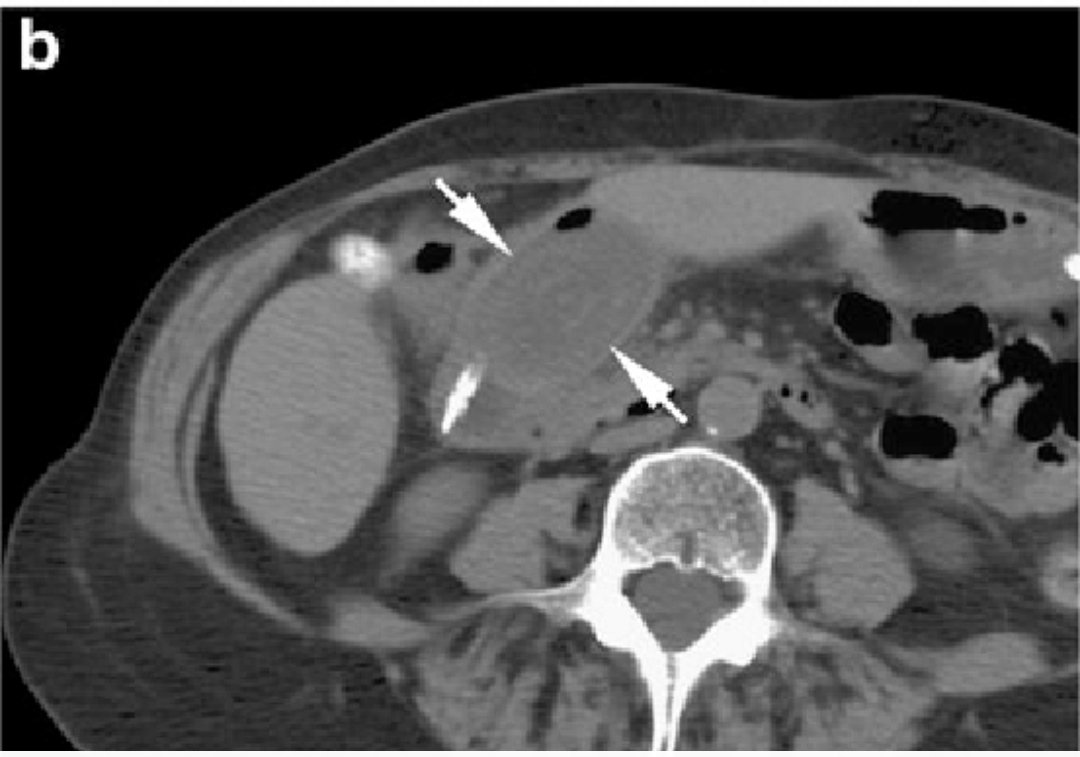

Bouveret syndrome in an elderly woman.

Abdominal radiograph (a) demonstrates

👉pneumobilia (curved arrow)

👉 gallbladder luminal gas (wavy arrow) secondary to a biliary-enteric fistula

👉 broad curve of the nasogastric tube (arrowheads) reflects gastric distension

CT image (b) demonstrates

👉a large gallstone (arrows) at the gastric outlet Image